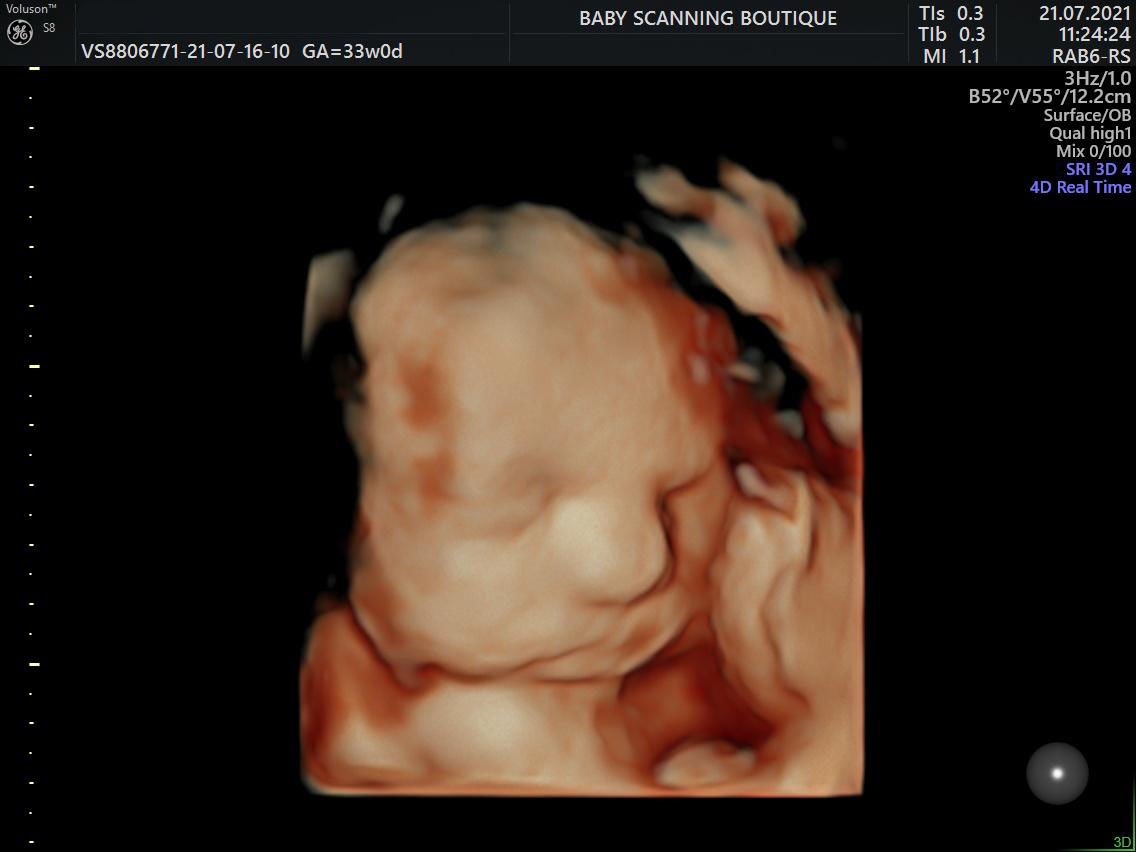

These are usually the 2D black and white scan images you are probably used to seeing in the hospital. This is because at this early stage baby isn’t yet developed enough to see in more detail. The same technology (ultrasound machine and probe) is used later in your pregnancy but is capable of showing you much more detail once your baby is sufficiently developed, usually this is possible from around 16 weeks but best images are taken around 27 weeks. These are the high detail 3D pictures that have a golden look and feel to them.

HD Live is an enhanced version of a 3D scan using the latest GE technology available on only the newest machines to render amazingly realistic images of your baby. It uses the most recent generation of beamforming technology combined with speckle reduction algorithms and virtual light sources to create lighting and shadowing effects. This means our sonographer can incorporate light and shadow on baby’s face just as you would see in a person standing next to you.

Our 3D and 4D bonding scans allows you see your baby at an enhanced level of detail, meaning you can see things that cannot be seen in traditional 2D format such as sucking their thumb, smiling, blowing bubbles or opening their eyes.

The perfect time for a 4D bonding scan is between 26-31 weeks because of the optimal balance between baby development and womb conditions but 4D scans can be done anytime from 14 weeks and even as late as 36 weeks we can still get amazing quality images.

The GE Voluson ultrasound machine we use is a very sophisticated piece of technology, its widely recognised worldwide as for providing the best 4D images and you’ll be amazed by the depth of clarity and detail it shows off. In 4D its possible to see your baby do things like sucking their thumb, opening their eyes, blowing bubbles, smiling etc… perfect to start getting to know your baby before he/she is even here.